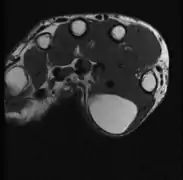

A physical exam is typically the easiest way to diagnose it. Rarely, a tissue biopsy or imaging may be required. The imaging modality of choice is magnetic resonance imaging (MRI), because it has superior sensitivity of distinguishing it from liposarcoma as well as mapping the surrounding anatomy.[20]

MRI showing lipoma of the arm